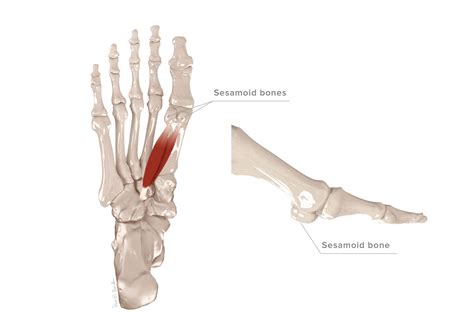

The sesamoid bones are small, round bones embedded within tendons. In the foot, there are two sesamoid bones located beneath the head of the first metatarsal bone, which is the long bone connected to the big toe. These bones are named the medial and lateral sesamoid bones, and they act as pulleys for the tendons that control the big toe.

The primary function of the sesamoid bones is to enhance the mechanical advantage of the tendons by increasing the leverage and reducing friction. This allows for more efficient movement and weight distribution during activities such as walking, running, and jumping. The sesamoid bones also help to absorb shock and distribute weight evenly across the foot.